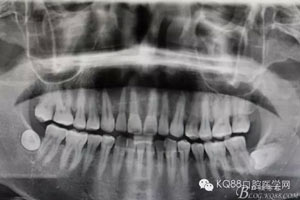

患者、張xx、男、35歲。主訴:右側(cè)上頜前牙唇側(cè)、腭側(cè)牙床腫脹半月。??茩z查:11、12、13唇側(cè)牙齦紅腫。捫診溢膿,腭側(cè)粘膜隆起。x線全景片檢查:14至21的遠(yuǎn)中根尖有一橢圓形囊性陰影,范圍約3.5x4.5cm,邊界清楚。治療計(jì)劃:1.行11、12、13根管治療。2.抗感染治療一周。3.炎癥消退后,行囊腫摘除術(shù)。患者同意治療方案,簽知情同意書。

圖1.術(shù)前全景片檢查:11、12、13根尖區(qū)橢圓形陰影,邊界清楚,單囊影。初步診斷:頜骨囊腫